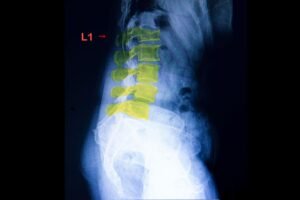

Как изглежда спондилолистезата на образно изследване

Спондилолистезата най-често се установява чрез образни изследвания като рентгенография или MRI. Тези изследвания позволяват да се види позицията на прешлените и дали има приплъзване между тях.

На рентген или MRI може да се наблюдава:

приплъзване на един прешлен спрямо друг

промени в междупрешленния диск

стеснение на пространството около нервните структури

дегенеративни промени в ставите на гръбначния стълб

Образните изследвания дават важна информация за структурата на гръбначния стълб, но винаги трябва да се интерпретират заедно със симптомите на пациента.